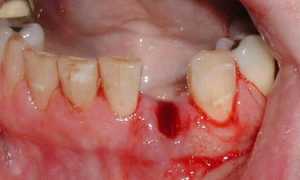

Фото 1. Воспаление десен – причиной может стать распространение бактерий от больных зубов во время операции.

В первом случае, во время операции по удаления зуба, врач мог случайно повредить нервное окончание или оставить в ранке осколок зуба. Если это произошло, рекомендуется повторно обратиться в больницу, для обнаружения точной причины неприятного последствия. Для устранения проблемы придётся прибегнуть к оперативному вмешательству.

Если причиной зуда и чувствительности стало воспаление слизистой, значит рядом с опустевшей лункой находится зуб, поражённый кариесом. Во время операции по удалению восьмёрки врач обязательно санирует полость рта, но это не даёт гарантии того, что болезнетворные бактерии не попадут в ранку.